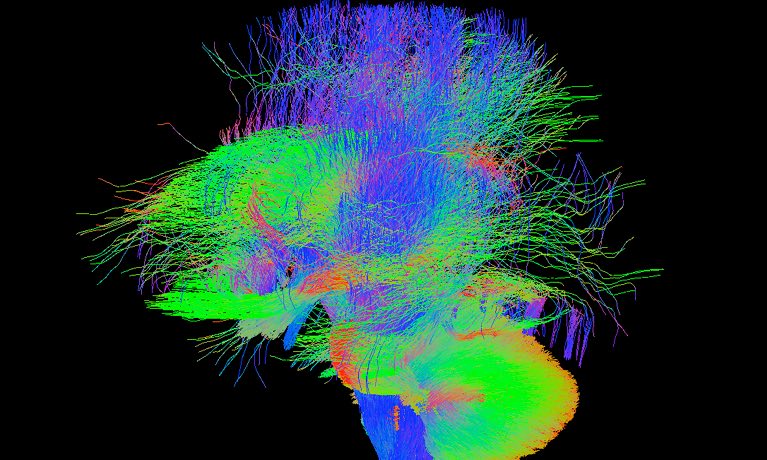

Probing the Brain’s Subtle Wiring

The project’s ultimate goal is to create the first 3D map of the gestational human brain from 20 weeks onward. They will create the map using millions of images, one taken each second, which they will then stitch together into a coherent whole. Some of the babies in the study are identified as being at a high risk of developing autism and other neurological disorders. Researchers will ideally be able to create 3D maps of high risk and average risk brains for comparison.

In the longer term, the researchers hope to have both genetic and medical data for the babies, along with their test results as they grow older. This holistic, long-term view of brain development and health outcomes would afford scientists unprecedented insights into how even the most subtle changes in the anatomy and wiring of the brain might influence health and behavior later in life, perhaps leading to new avenues of treatment for various disorders.